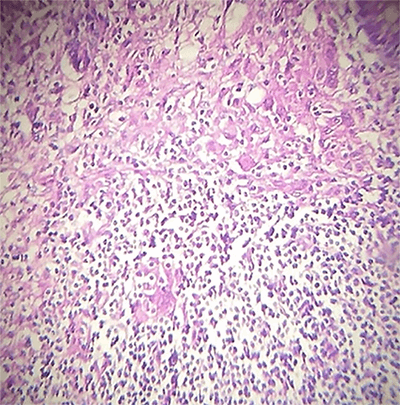

Our patient is a 33-year-old female with a past medical history of rheumatoid arthritis and hypothyroidism. She presented to the emergency department with fever and intense abdominal pain, having experienced one week of abdominal pain and asthenia. Upon presentation, she was found to be hypotensive but responded to crystalloid resuscitation. She had no leukocytosis or evidence of acute blood loss anemia. Ultrasound demonstrated free fluid in the abdomen, but the appendix couldn’t be seen. The patient was taken for diagnostic laparoscopy, where we found serous fluid in the abdominal cavity, multiple lymph nodes at the root of the mesentery, and an enlarged appendix. An appendectomy was performed, and culture of the fluid was taken. Microbiology reported a multi-sensitive E. coli. The patient was treated with six days of ampicillin and had an uneventful recovery. When seen in follow-up two weeks postoperatively, the patient was doing well and had no specific symptoms. The pathology report described a granulomatous appendicitis (Figure 1).

Figure 1. Granulomatous appendicitis, Submucosa granulomas surrounded by necrotic center around histiocytes.

Classic pathological analysis of granulomatous appendicitis usually reveals the presence of caseating granulomas and Langhans giant cells as it was found in our patient.3